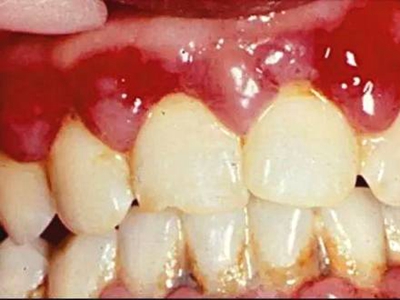

急性坏死性溃疡性龈炎起病急,病程短,常为数天至1-2周,以龈乳头和龈缘的坏死为其特征性损害,尤以下前牙多见,初起时龈乳头充血水肿,个别龈乳头顶端可发生坏死性溃疡,上覆有灰白色坏死物,中央凹下如火山口状。龈缘如虫蚀状,坏死区出现灰褐色假膜,擦去后可见出血创面。龈乳头被破坏后与龈缘成一直线,如刀切状。病损一般不波及附着龈,患处牙龈极易出血,疼痛明显并有腐败性口臭。